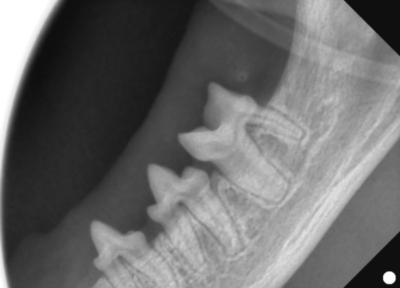

そして歯科レントゲン撮影を行いました。

なにがなにやらわからないと思い、黄色ラインで歯をなぞりました。右上顎です。中央に過剰な歯があり、回転して生えています。

左下顎は正常な数と歯並び

右上顎も同様に中央に回転して生えている過剰歯があります。

左下顎は中央に重なって生えている過剰歯があります。レントゲンで確認しても、乳歯ではなく永久歯と考えられました。これらは過剰歯と呼ばれ、通常より本数が多く歯が生えてきます。かみ合わせが悪くなり、また歯間が狭くなり歯垢がつき、歯周病になりやすいです。そのため、不必要と思われる歯を抜歯しました。また、歯肉の増殖している部分を一部切り取り病理検査用の検体とし、それ以外の部分はメスで切除し正常に近い歯肉の形状に近づけました。